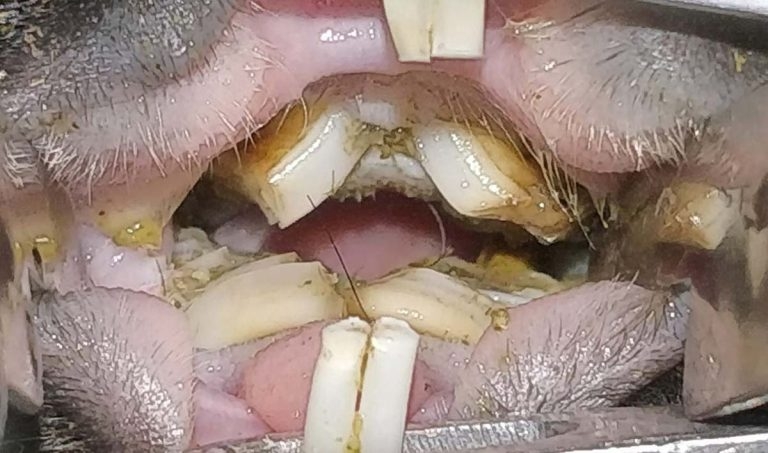

Figure 2. A typical presentation of overgrown bridging molars in a guinea pig. This impedes their ability to swallow.

Due to the mechanism of overgrowth within the mouth causing molars to bridge over the tongue, guinea pigs will often lose the ability to swallow effectively or at all (Figure 2). This often leads to ptyalism.